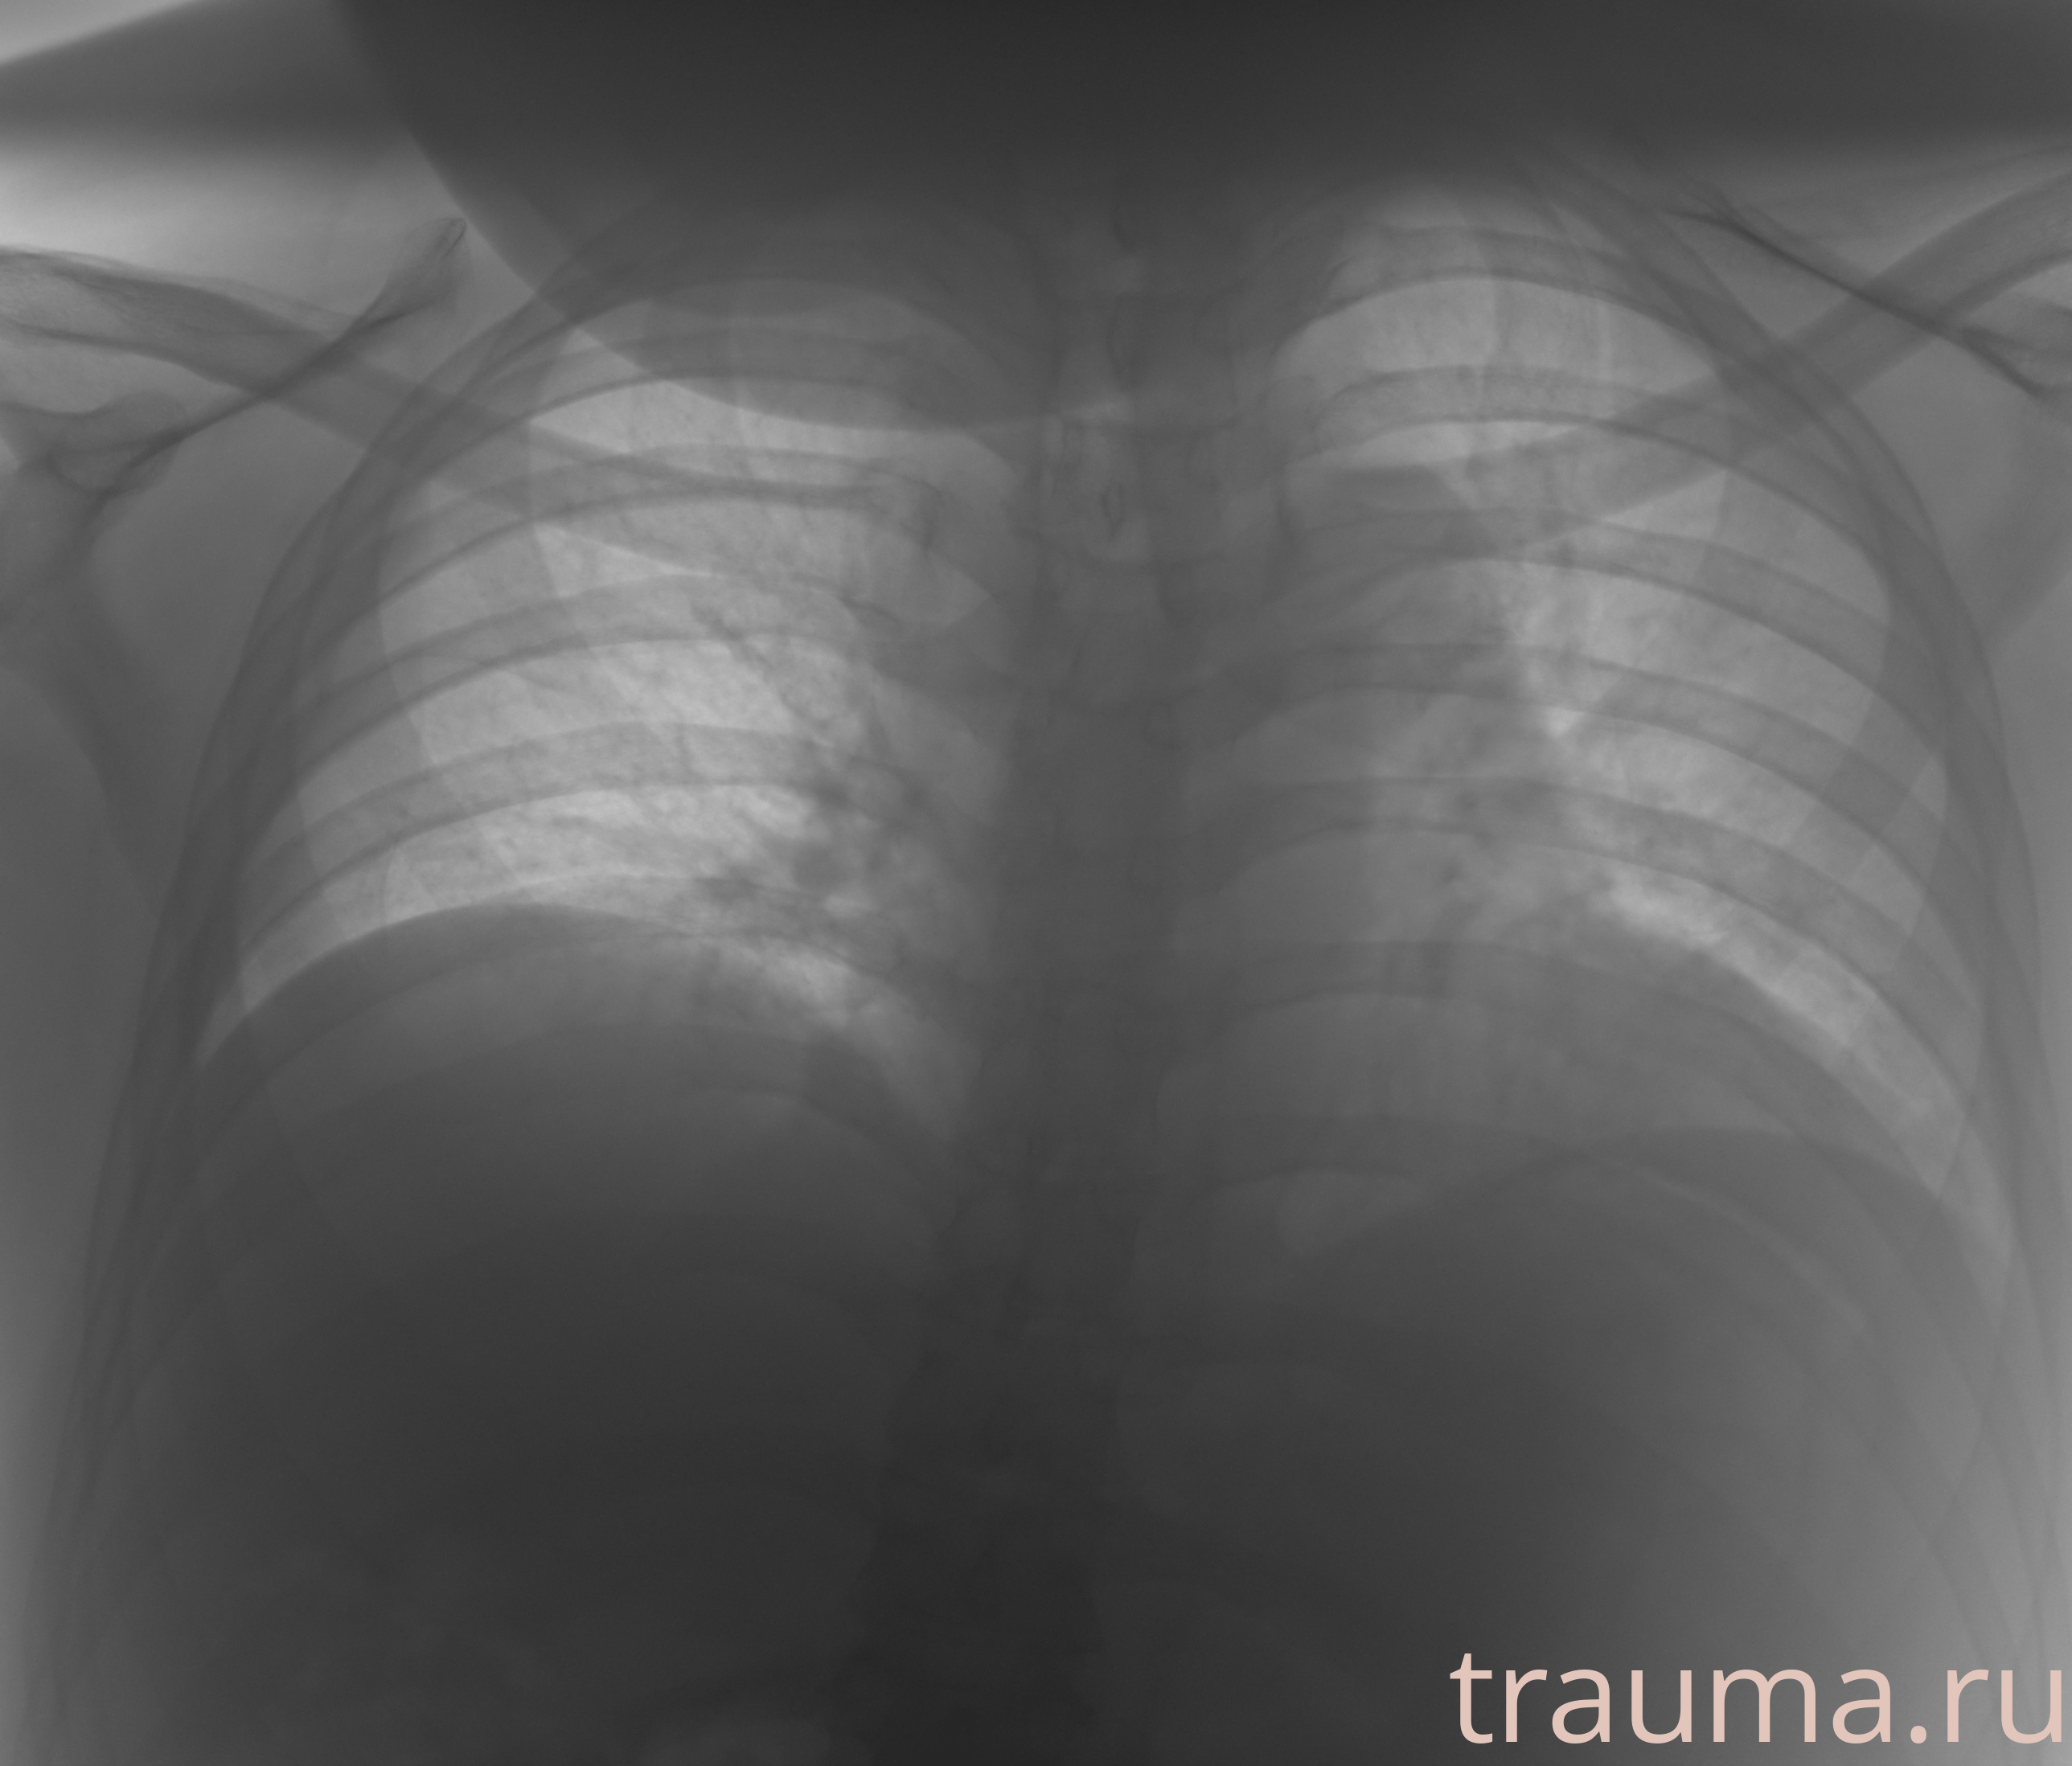

Рентгенограммы

Рентген на дому: по вашему адресу приезжает врач-рентгенолог, травматолог-ортопед с мобильным рентгеновским аппаратом, проводит диагностику травмы или заболевания, делает необходимые рентгенограммы, дает рекомендации по дальнейшему лечению. Получить качественные снимки в домашних условиях возможно благодаря уникальной методике, разработанной МосРентген Центром для института  Склифосовского